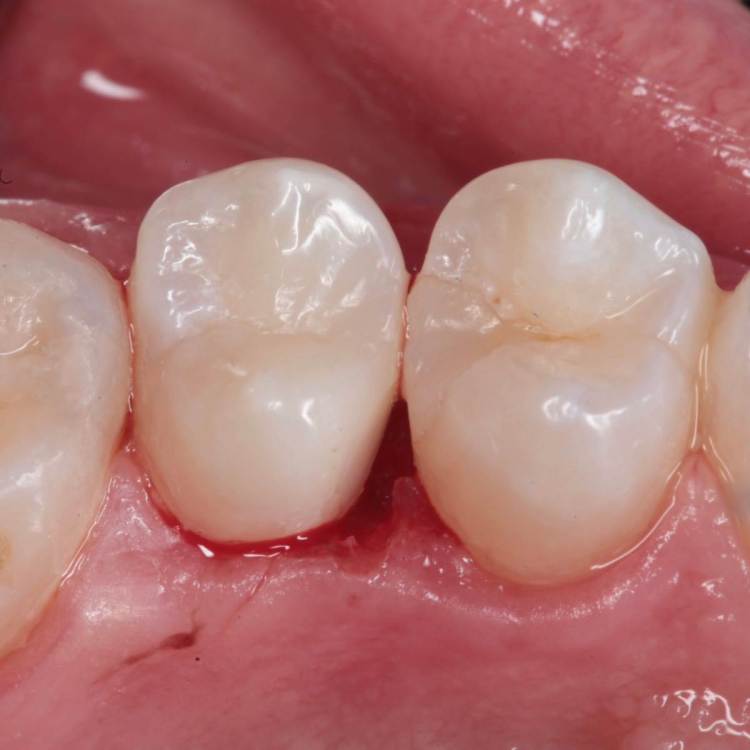

Как часто мы сталкиваемся с такими процессами и как редко пациент сам предъявляет какие то жалобы на такие зубы. Максимум это… застревание пищи.

Глубина полости ниже уровня десневого края на 2-3 мм. Коагуляция, ENDO, анатомичный билдап, проверка качества реставрации и отсутсвие нависающего края (интерпроксимальный снимок), рекомендации.